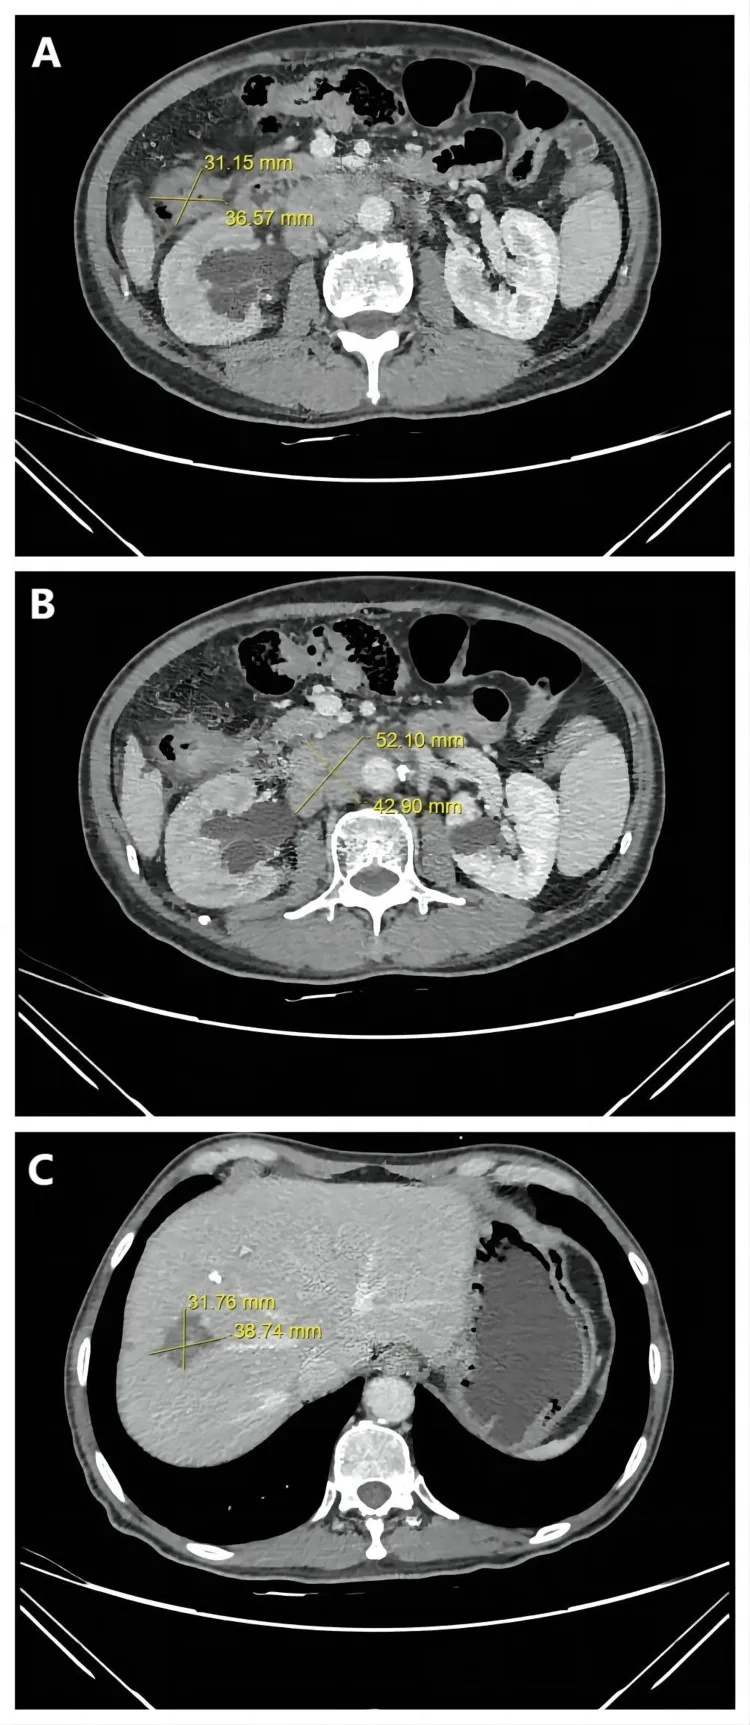

2、病灶全面缩小并达PR:相较于第二次治疗后“结肠及淋巴结病灶缩小、肝转移灶无变化”的情况,此次所有病灶均明显缩小——CT显示结肠肿瘤从3.7cm×3.1cm缩小至2.1cm×1.7cm,腹膜后淋巴结转移灶从5.2cm×4.3cm缩小至2.3cm×1.4cm,肝脏肿瘤从3.9cm×3.2cm缩小至2.9cm×2.3cm(详见下图)。肿瘤缩小至可手术切除的程度。术后,患者获得病理完全缓解(pCR)。

▼该患者第二次治疗后,腹部轴向CT图像

▲图源“Cureus”,版权归原作者所有,如无意中侵犯了知识产权,请联系我们删除